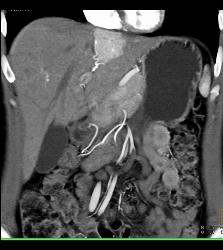

Focal Nodular Hyperplasia (FNH)